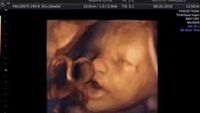

Seperti 'Bernyanyi', Begini Cara Janin Merespons Suara dari Luar